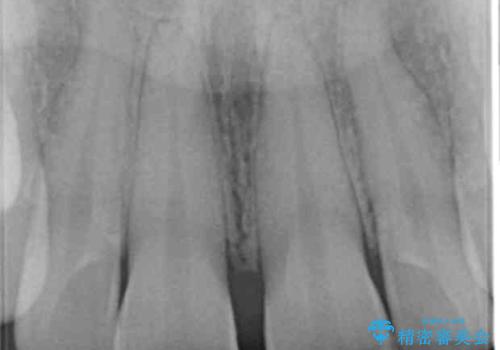

- 上の前歯の隙間を気にして来院された患者様です。

矯正治療により前歯を閉じるという治療を第一選択肢として提案しましたが、期間と費用からオールセラミッククラウンによる補綴治療を行うこととしました。

虫歯もない前歯を削ることは、処置をする者として心苦しいのですが、患者様は矯正治療は選択しないとのことだったので、オールセラミッククラウンにて補綴治療を行いました。